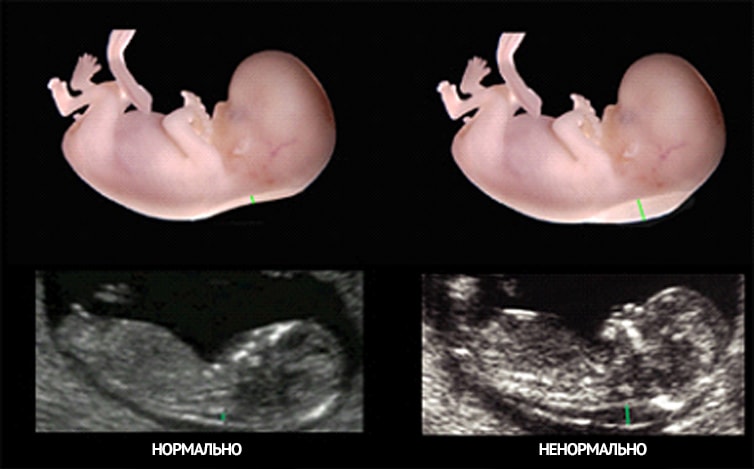

Вам какие то параметры эмбриона написали? пятно это скорее всего измерялась

Толщина воротникового пространства (ТВП) плода, один из важнейших маркеров при первом скрининге в 12 нед. Уточните у доктора, что с этим делом. конечно делать замеры и выводы не раньше 11 недели.